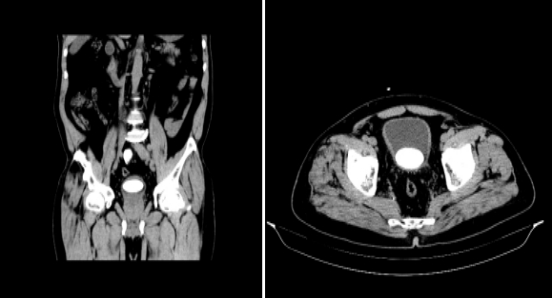

70歲的邵伯近半年來被反復(fù)的排尿困難所困擾,曾在當(dāng)?shù)匦l(wèi)生院就診,檢查結(jié)果是膀胱結(jié)石。最近更是癥狀加重,出現(xiàn)尿頻、尿急、尿痛、間斷血尿,家屬一籌莫展之時(shí),聽說我院有微創(chuàng)技術(shù)可以不開刀就解決“結(jié)石大痛苦”,決定帶著邵伯前來就診。入院完善CT檢查提示:膀胱巨大結(jié)石(4.5cm*3.5cm*3.5cm),如此巨大的結(jié)石,就算是在場(chǎng)經(jīng)驗(yàn)豐富的泌尿外科醫(yī)護(hù)們看了,也頗為震驚,但又怎會(huì)難倒“久戰(zhàn)沙場(chǎng)”的泌尿外科團(tuán)隊(duì)呢?周雄主任帶領(lǐng)團(tuán)隊(duì)展開充分術(shù)前討論,結(jié)合邵伯以及家屬的實(shí)際需求后,考慮為其行“經(jīng)尿道膀胱鏡下氣壓彈道碎石術(shù)”,術(shù)中操作順利,體內(nèi)的結(jié)石被一一粉碎,在后續(xù)精心的術(shù)后護(hù)理中,邵伯也逐漸自我感覺輕松了起來。